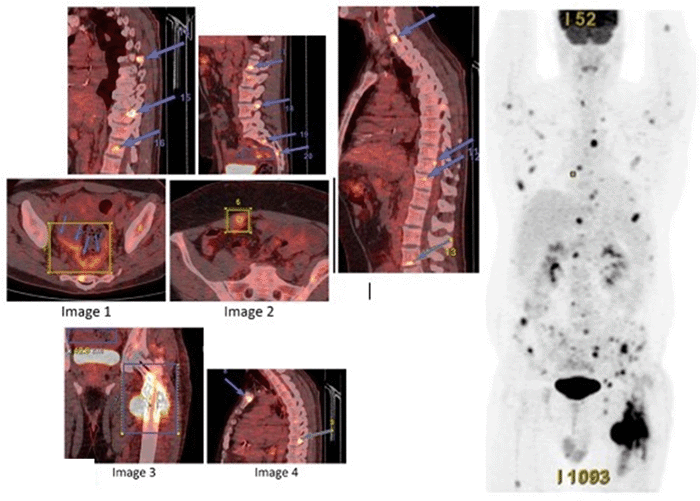

Computed tomography (CT) of the abdomen and pelvis confirmed a 6.8 cm sigmoid colon mass with imaging characteristics suspicious for osseous metastasis to the left proximal femur (Figure 1); no other intra-abdominal pathology or hepatic metastases were identified. A chest CT was negative for pulmonary metastatic lesions. Dedicated lower extremity imaging confirmed a pathological fracture of the femoral shaft. His preoperative carcinoembryonic antigen (CEA) level was elevated at 3.19 ng/mL.

Figure 1. Preoperative CT of Left Femoral Metastasis. Published with Permission